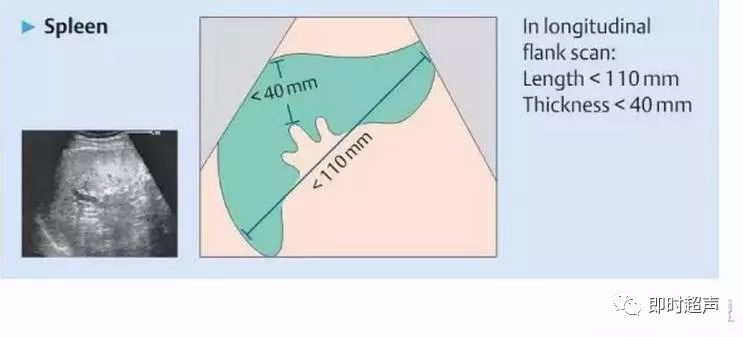

脾脏的测量及正常值:

(1)长度:即脾上极最高点至脾下极最低点间的距离,正常值范围为8-12cm。

(2)厚度:即脾门至脾门对侧缘最大的切线距离,正常值范围不超过4cm。

(3)宽度:为垂直于长轴切面上的最大横径,正常值范围为5-7cm。

图2 脾脏超声级规范测量